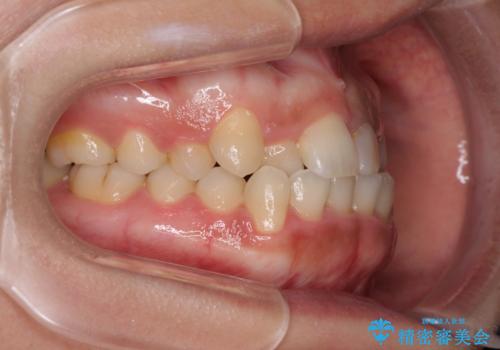

前歯の反対咬合 非抜歯のワイヤー矯正

- 前歯のでこぼこを気にして来院された患者様です。

マウスピース矯正の自己管理が面倒くさいことと、治療を早く終わらせたいとのことで、目立ちにくいワイヤー矯正にて歯列を整えることとしました。

1年半はかかると思っていた治療期間ですが、反対咬合となっている前歯が思いの外早く動き、僅か9ヶ月で終了させることができました。

前歯を気にせず笑えるようになり、患者様には大変満足していただきました。